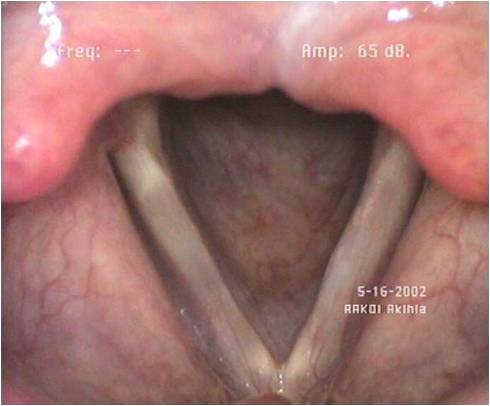

Voici deux images de larynx, 1 et 2 et deux sons de voix. A et B A quel larynx attribuez*vous chaque voix ?

Larynx1

Larynx1  Larynx2

Larynx2